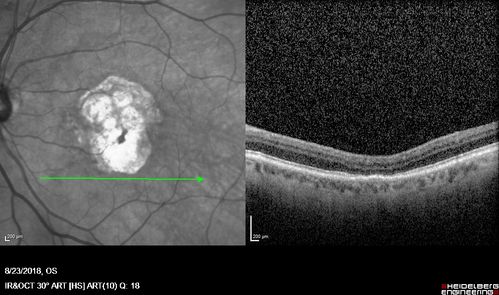

Outer Retinal Tubulation

78 year old man chronic wet AMD - 20/200

Outer Retinal Tubulation - Disciform Scar